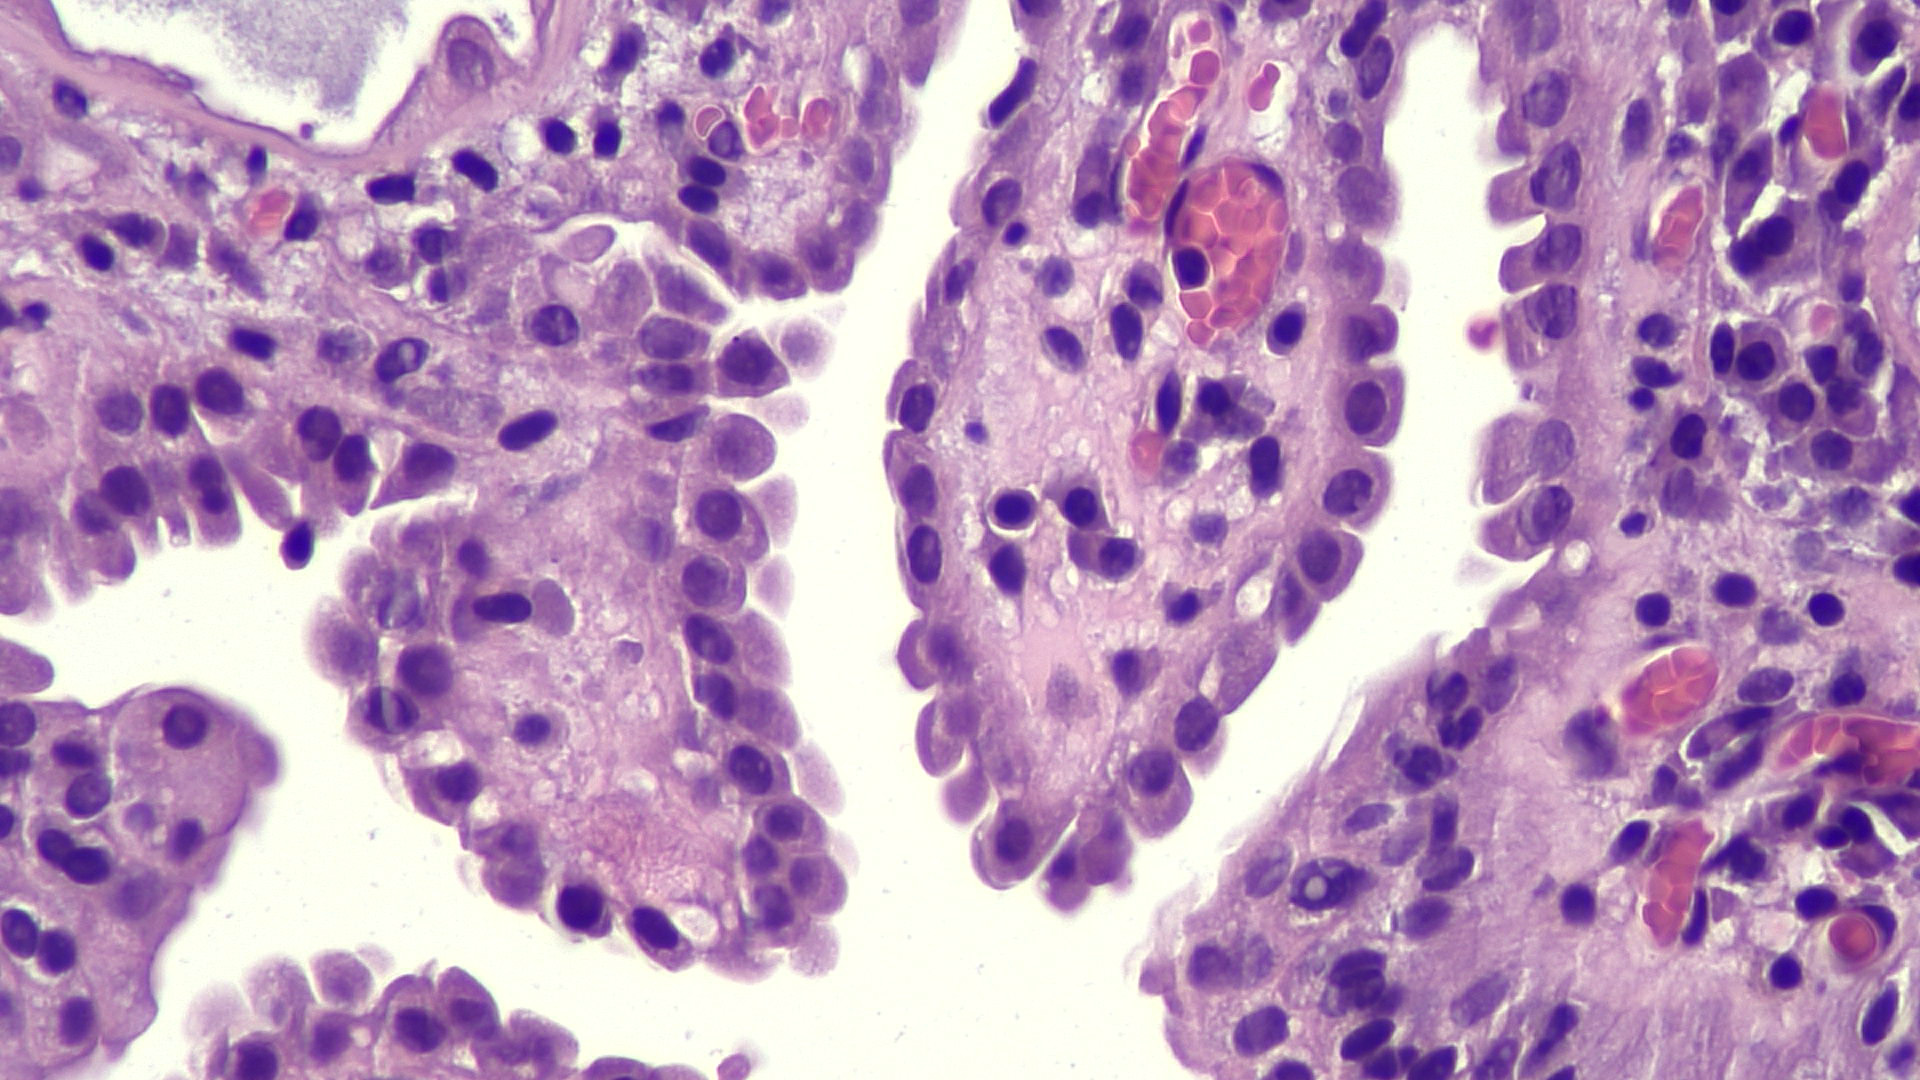

- Tubules lined by simple cuboidal, flattened or hobnail cells, forming an exophytic papillary or endophytic lesion (Urology 2016;95:29)

- Hyaline rim surrounds the tubules (PAS positive thickened basement membrane) (Adv Anat Pathol 2019;26:171)

- No mitotic activity

- Scant cytoplasm, finely granular uniform chromatin; usually inconspicuous nucleoli (Ann Diagn Pathol 2019;38:11)

- Only occasionally solid areas, rare clear cells, blue mucin within the tubules present

Microscopic (histologic) images